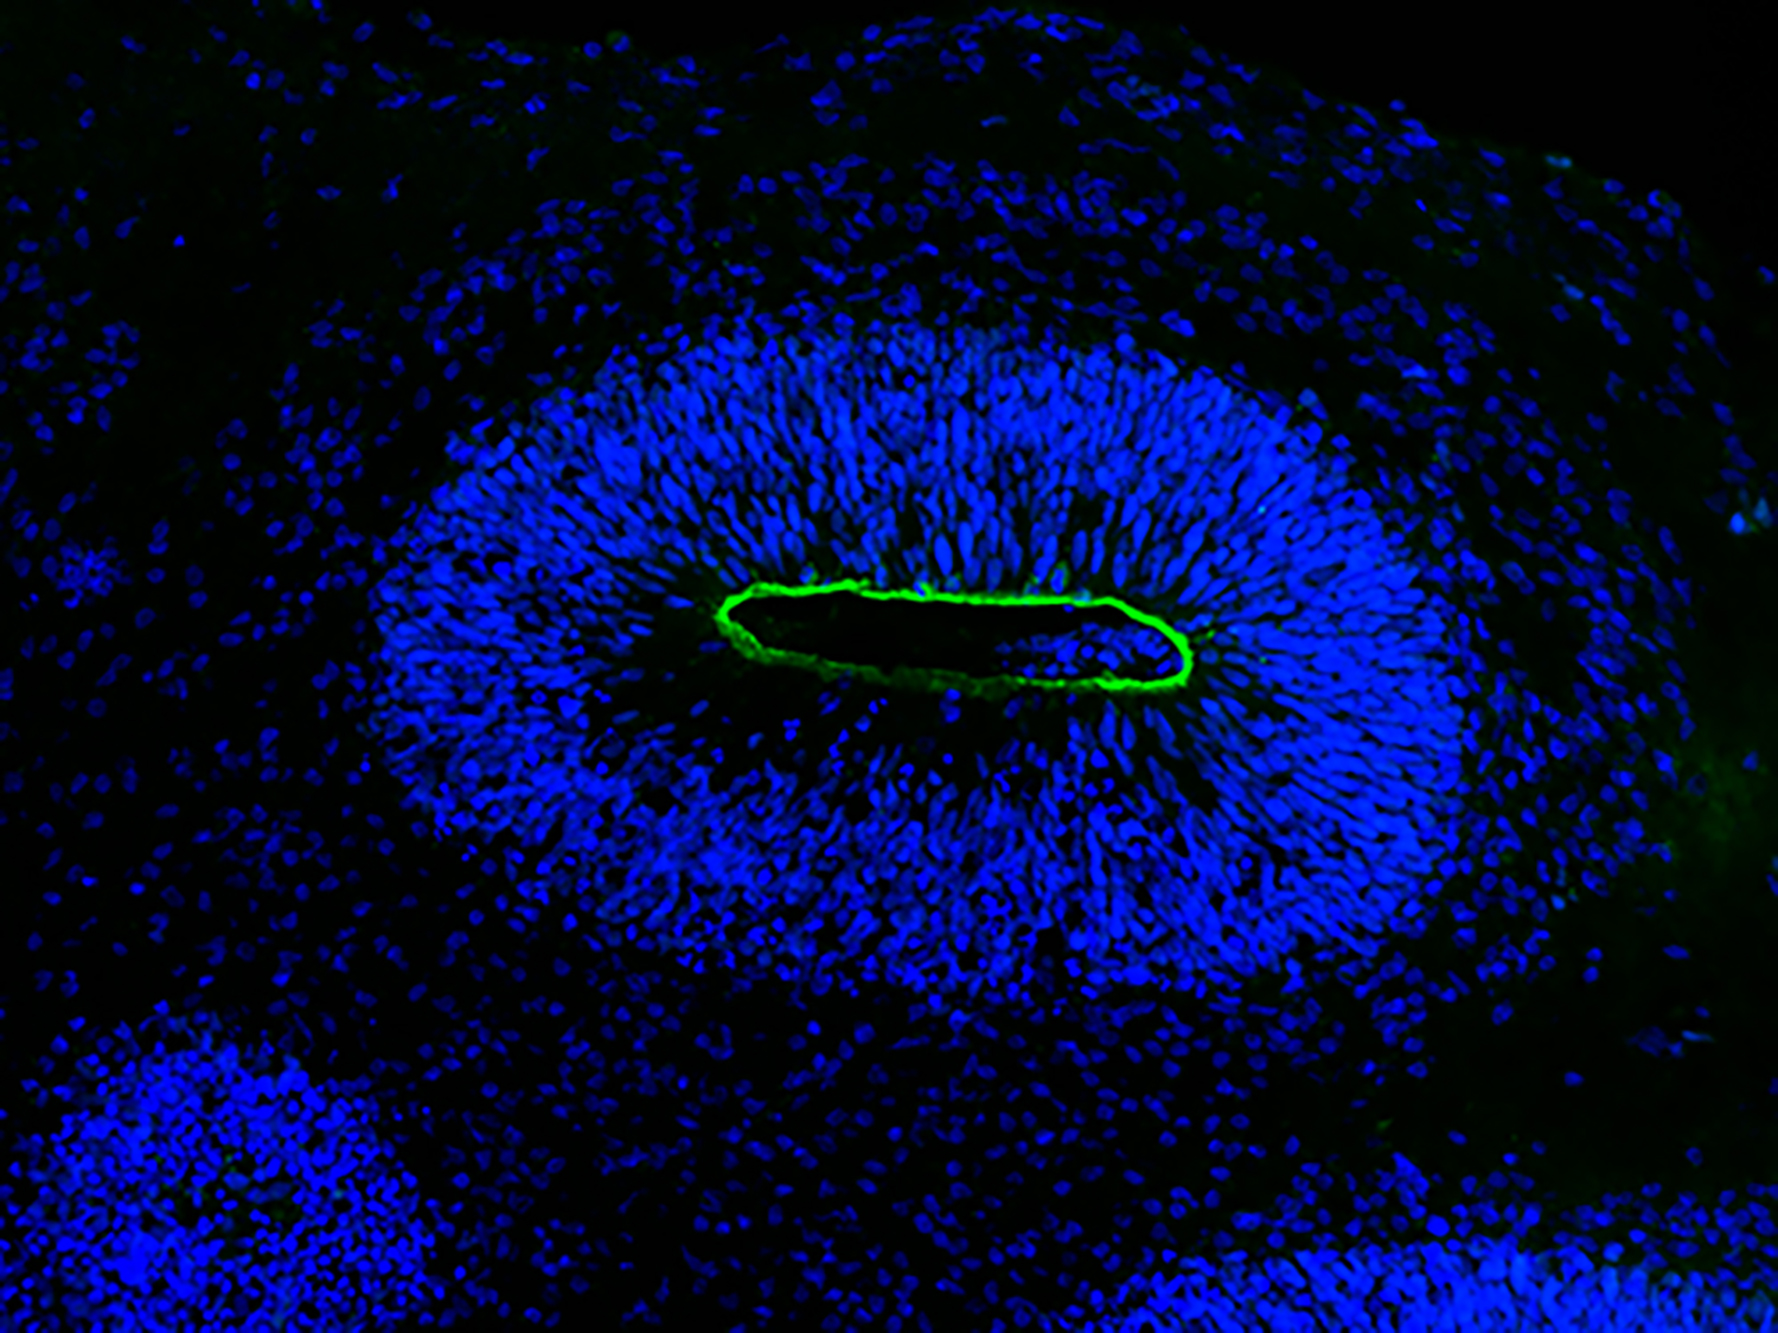

Die Wissenschaftler*innen haben die Organoide zunächst mit HSV-1 infiziert. Während das Virus wütete und die Mini-Hirne zerfielen, färbte das Team Neuronen und Neuroepithel an und machten das Schicksal der Zellen sichtbar. „Da sind wunderschöne Mikroskopie-Bilder entstanden. Sie machen sehr deutlich, was wirklich im Gewebe passiert“, sagt Wyler.